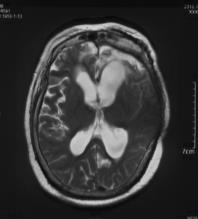

复阅2018年12月27日MRI片:左侧额颞部颅骨修补术后改变,两侧额颞叶、右侧小脑半球、左侧侧脑室后角旁均见长T1长T2异常信号,脑室系统扩大。提示左侧额颞部颅骨修补术后,两侧额颞叶、右侧小脑半球、左侧侧脑室后角旁软化灶形成。

图7-12,2018年12月27日MRI片,左侧额颞部颅骨修补术后,两侧额颞叶、右侧小脑半球、左侧侧脑室后角旁软化灶形成